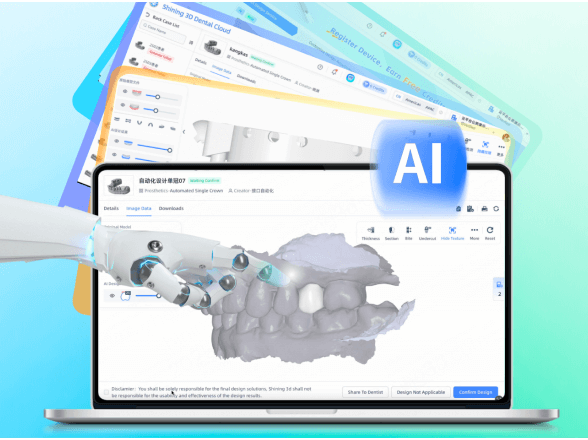

AI Crown

Intelligently generates dental crowns, auto-filling undercuts with meticulous precision.